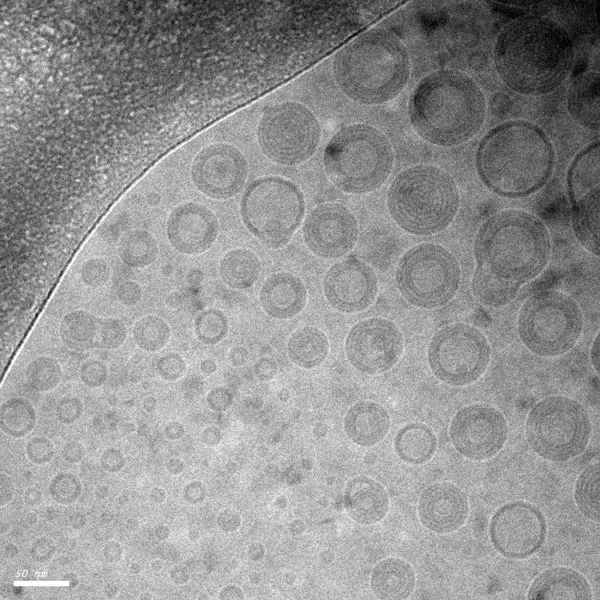

Cryoelectron microscope image of the nanoparticles developed by MIT researchers to deliver vaccines to mucosal surfaces.

Caption: Cryoelectron microscope image of the nanoparticles developed by MIT researchers to deliver vaccines to mucosal surfaces.

To create better ways of delivering such vaccines, Irvine and his colleagues built upon a nanoparticle they developed two years ago. The protein fragments that make up the vaccine are encased in a sphere made of several layers of lipids that are chemically “stapled” to one another, making the particles more durable inside the body.